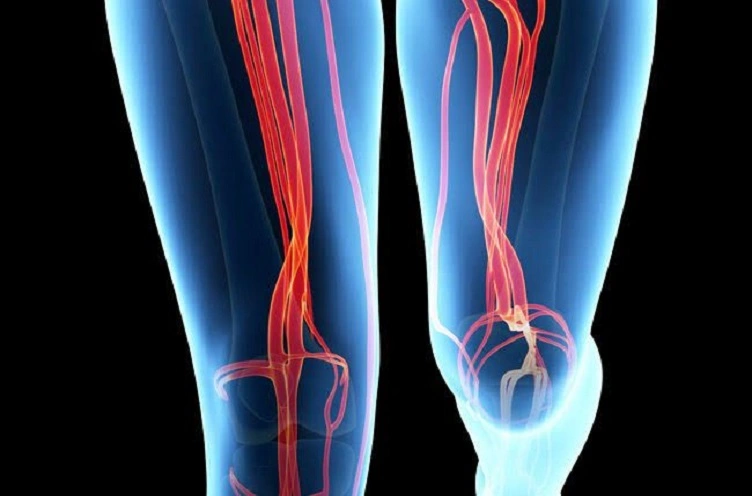

Una angioplastia coronaria es un procedimiento para abrir arterias coronarias estrechas o bloqueadas. El Dr. Sergio Alberto Rodríguez López la realiza para mejorar el flujo sanguíneo en el corazón y se recomienda en casos de enfermedad coronaria significativa.